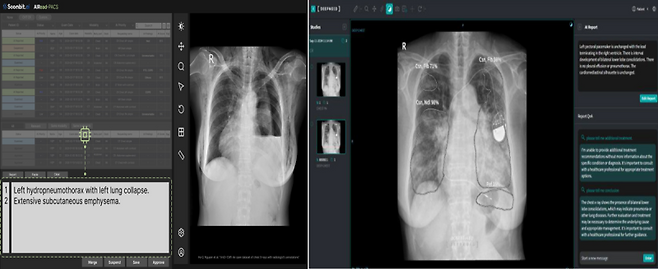

흉부 X-ray 영상을 분석해 예비소견서를 생성하는 소프트웨어인 숨빗AI 'AIRead-CXR'가 3등급 의료기기로 승인을 받은 것이다.

흉부 X-ray 영상을 분석해 예비소견서를 생성하는 소프트웨어인 숨빗AI 'AIRead-CXR'가 3등급 의료기기로 승인을 받은 것이다. 이와 함께 딥노이드(315640) 'M4CXR'도 지난해 11월 자사 M4CXR 임상시험을 마치고 식약처 품목 허가 결정을 기다리고 있다.

단순 질환 의심 부위 표시나 중증도 수치화를 넘어, 57종의 이상 소견을 분석해 전문의 수준의 텍스트 ‘예비소견서’를 직접 작성해 주는 이 기기는 글로벌 의료기기 규제 역사에서도 이례적인 선도 사례로 꼽힌다. 과연 글로벌 의료 강국들과 비교해 이번 국내 첫 허가가 갖는 의미는 무엇일까.